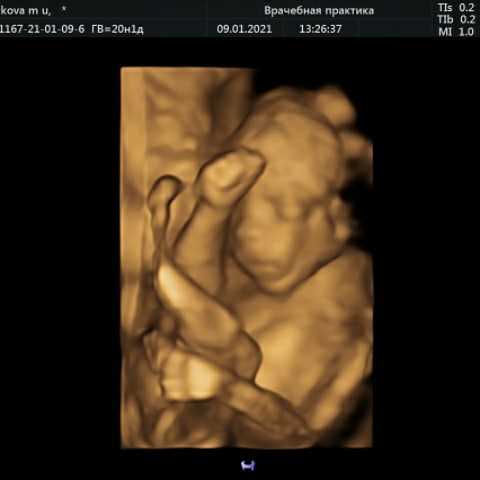

Вот мы и сходили на узи. У нас богатырь!))

Оригинально ножки сложил)))

Он у нас вообще загнулся)